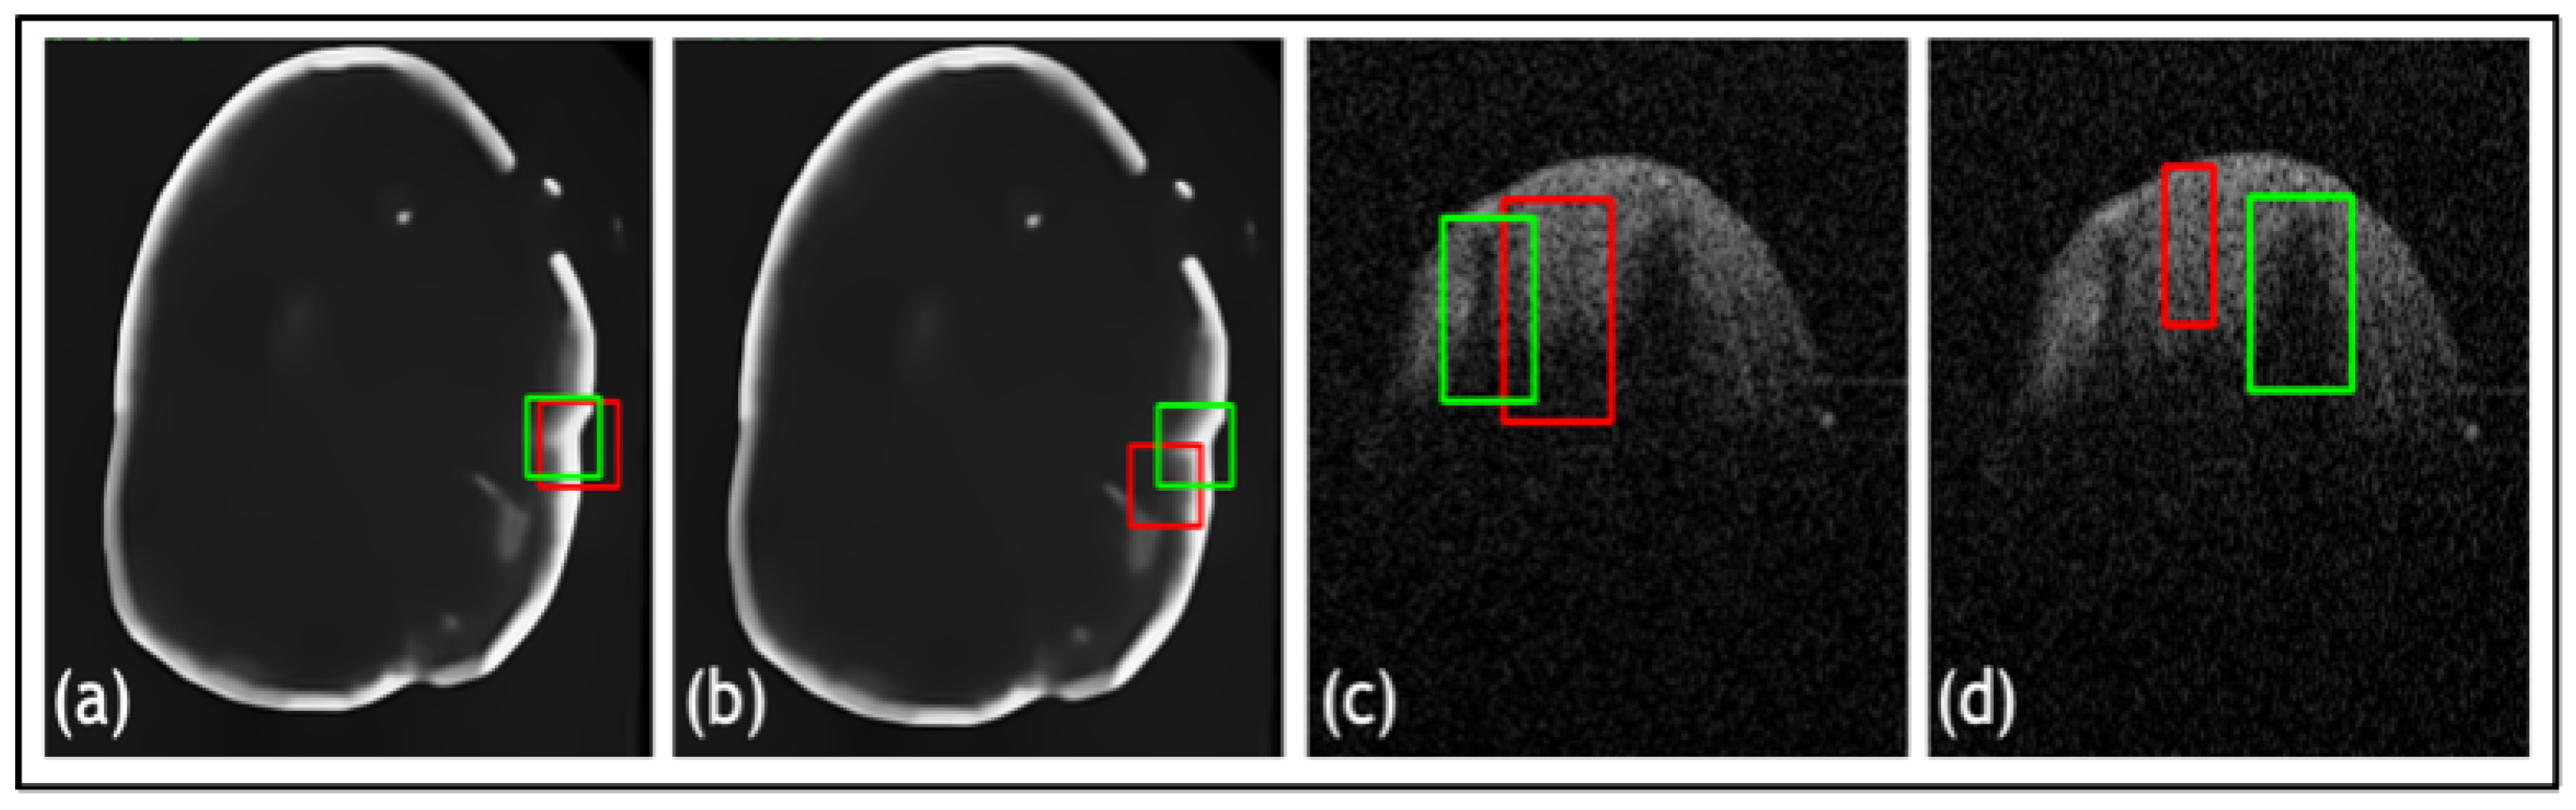

- A novel TED framework is developed, focusing on detecting relevant lesions in noisy OCT images of different organs.

- In TED, the transformer is adapted to take in images and slide across Regions of Interest (ROIs) provided by AGs. This design aims to adaptively deal with different types of noise artifacts and thus effectively detect a variety of anomalies including tooth decay and numerous lesions across two modalities.

- A new loss function is proposed along with TED, which combines a sliding box, Intersection Over Union (IOU), and Mean Squared Error (MSE). It compares the IOU and MSE between the predicted and real bounding boxes to evaluate the regions of focus chosen by the AGs.